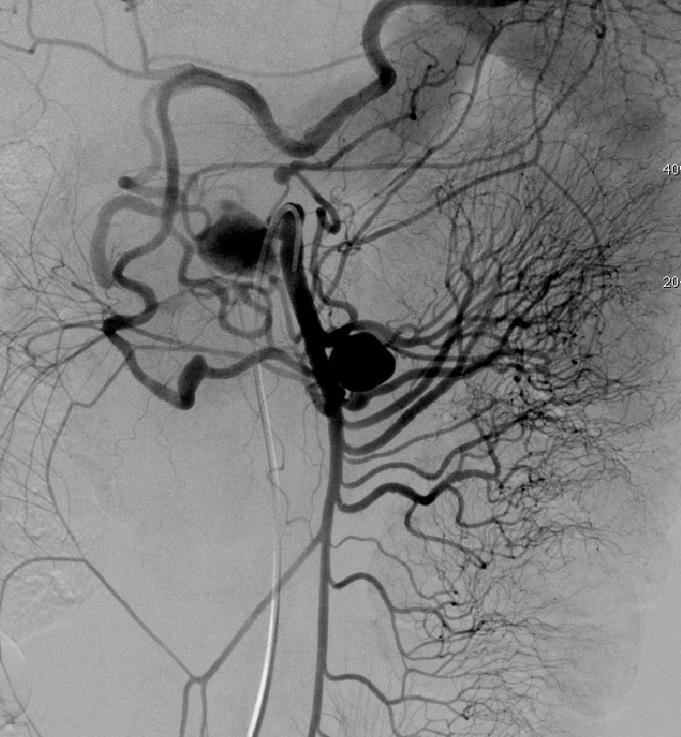

肺动静脉畸形的栓塞(锚定和脚手架技术)

肺动静脉畸形 |

利用锚定技术将弹簧栓子头端释放到肺动脉其中一支后,其余部分释放到血管内 |

栓塞术后造影 |

肺动静脉畸形的栓塞

肺动静脉畸形CT |

肺动静脉畸形血管造影(动脉显影) |

|

肺动静脉畸形血管造影(静脉显影) |

肺动脉栓塞后 |